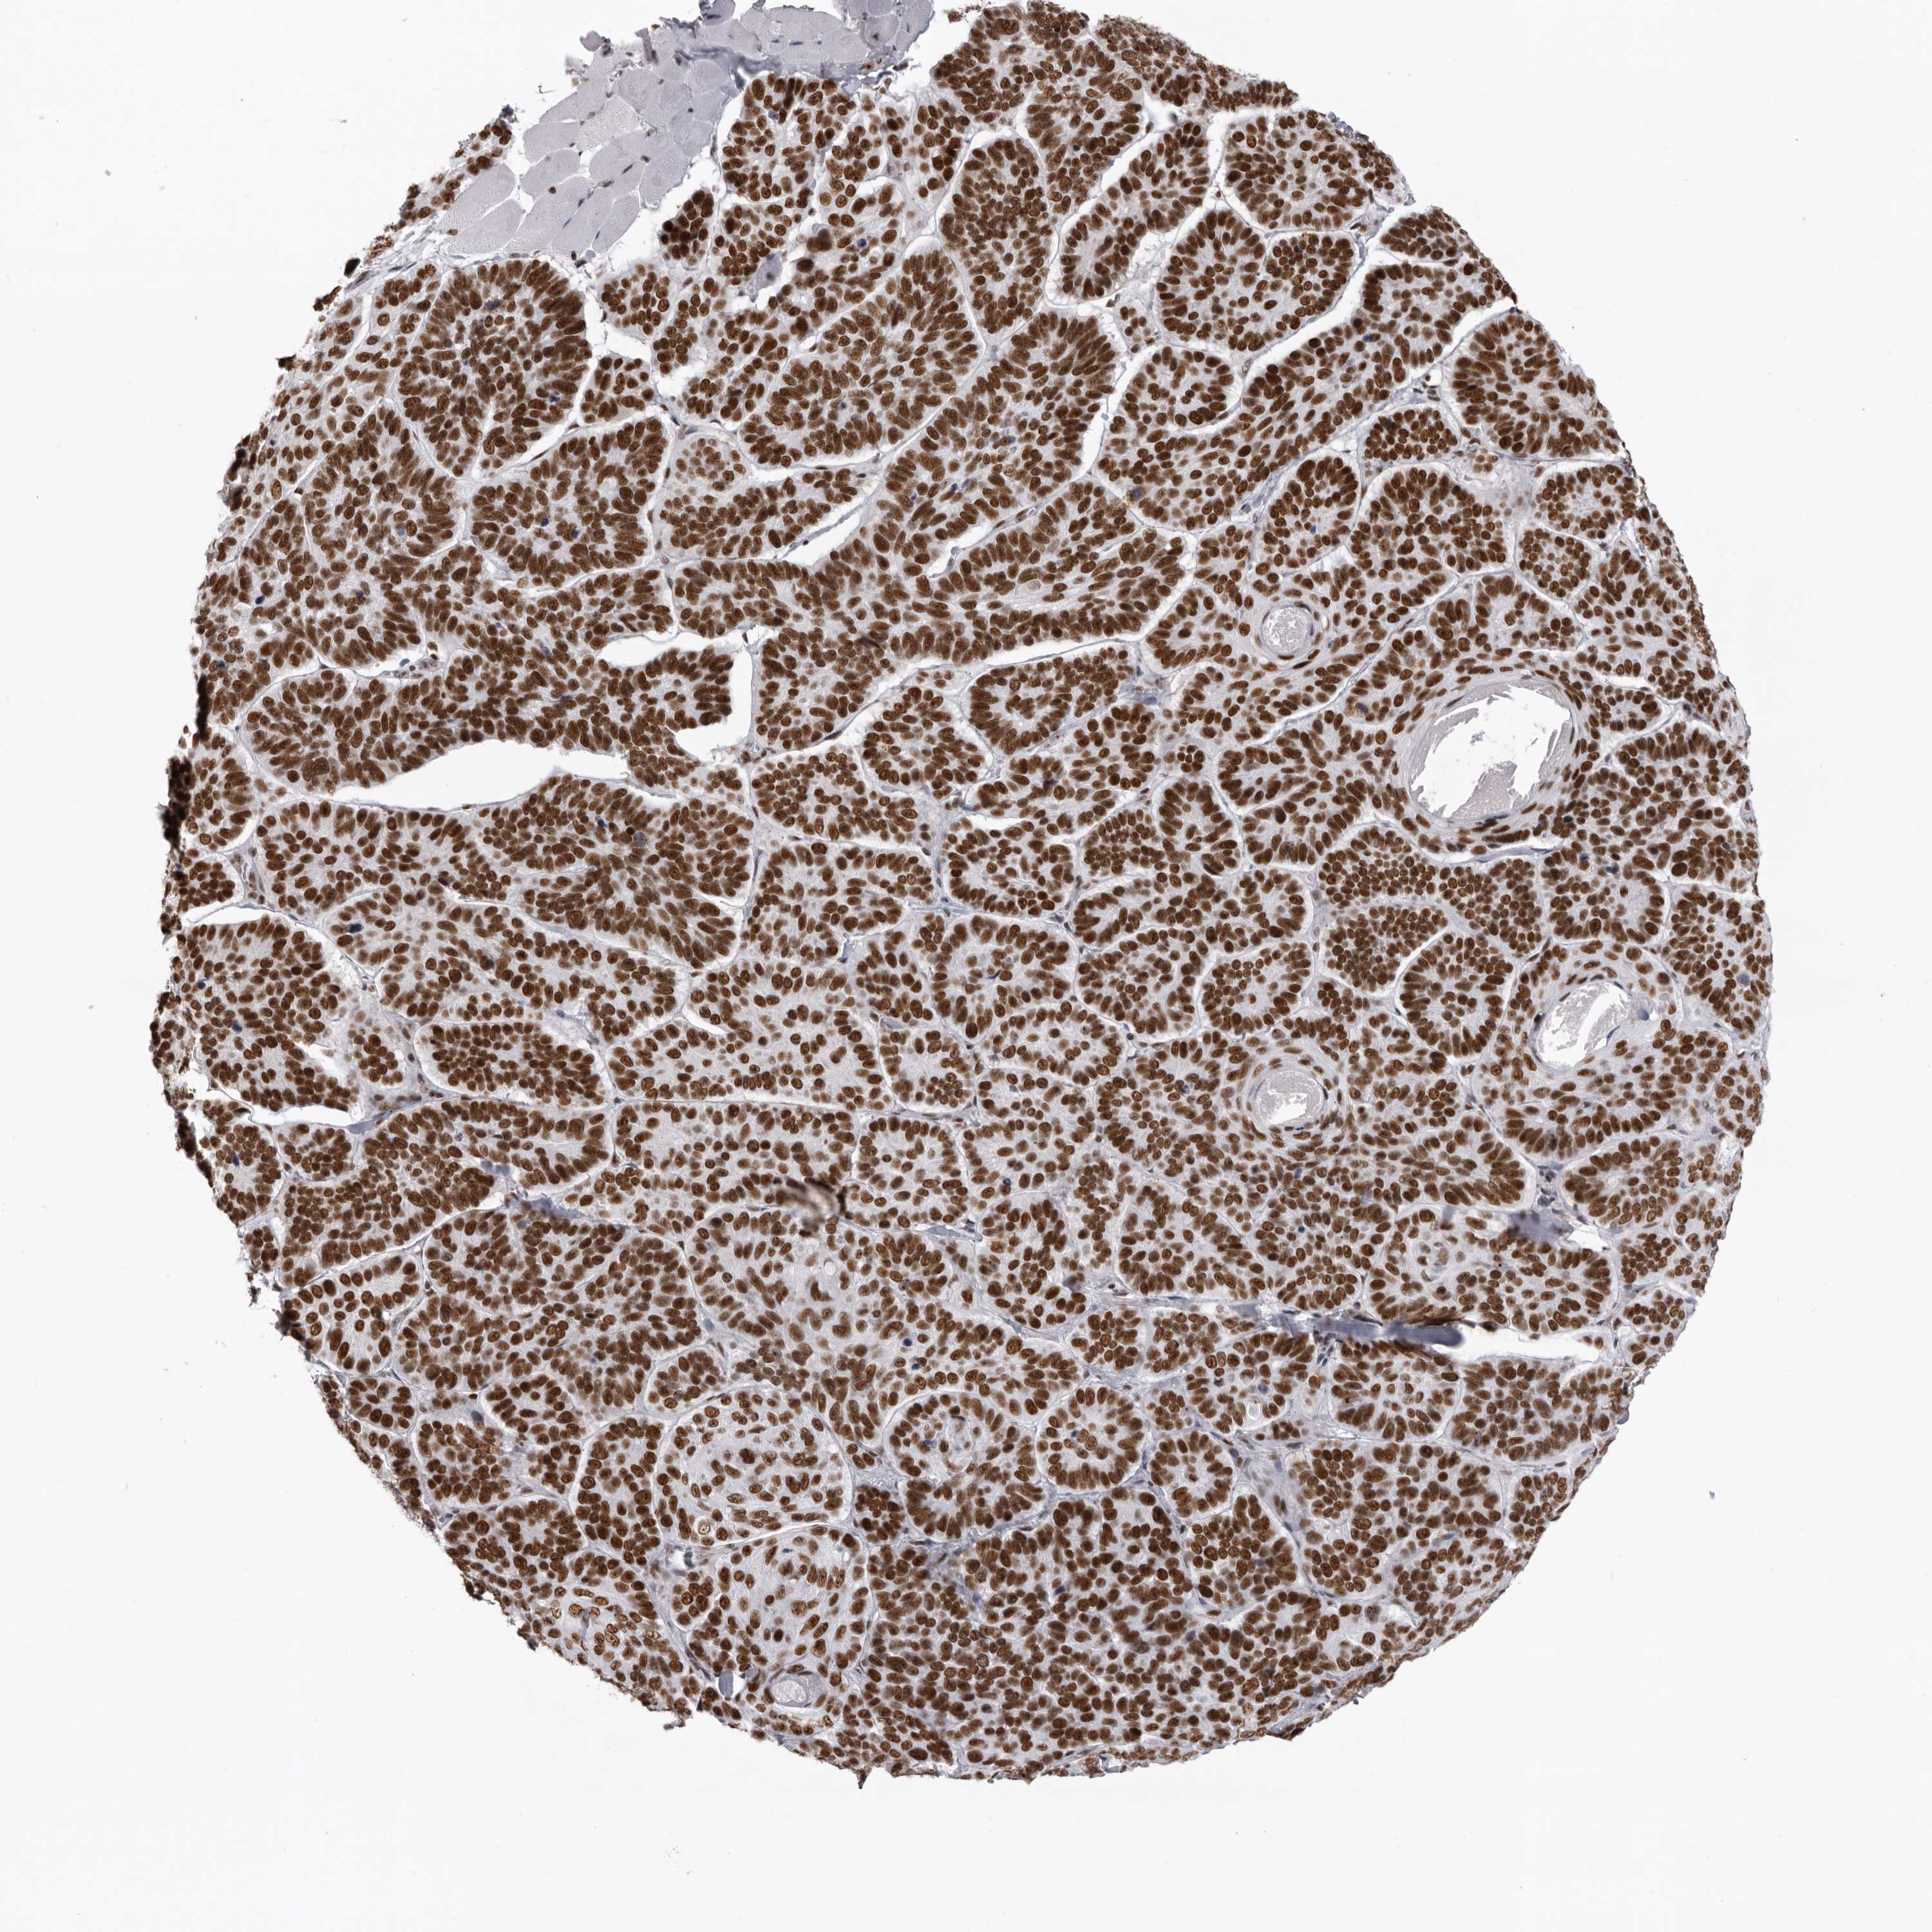

SKIN CANCER - Protein expressioni

A mouse-over function shows sample information and annotation data. Click on an image to view it in a full screen mode. Samples can be filtered based on level of antibody staining by selecting one or several of the following categories: high, medium, low and not detected. The assay and annotation is described here.

Each image is clickable and will lead to virtual microscopy that enables deeper exploration of all samples and also displays staining intensity scores, fraction scores and subcellular localization as well as patient and tissue information for each sample.

Antibody CAB011819

Staining

High

Intensity

Strong

Quantity

>75%

Location

Nuclear

Basal cell carcinoma

Adnexal tumor, benign